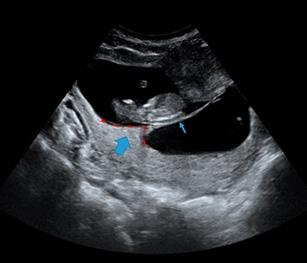

Figura 18. El cordón umbilical Corte transversal del cordón umbilical a la ecografía donde se evidencia el “Signo de Mickey Mouse” (AU: arteria umbilical, VU: vena umbilical)